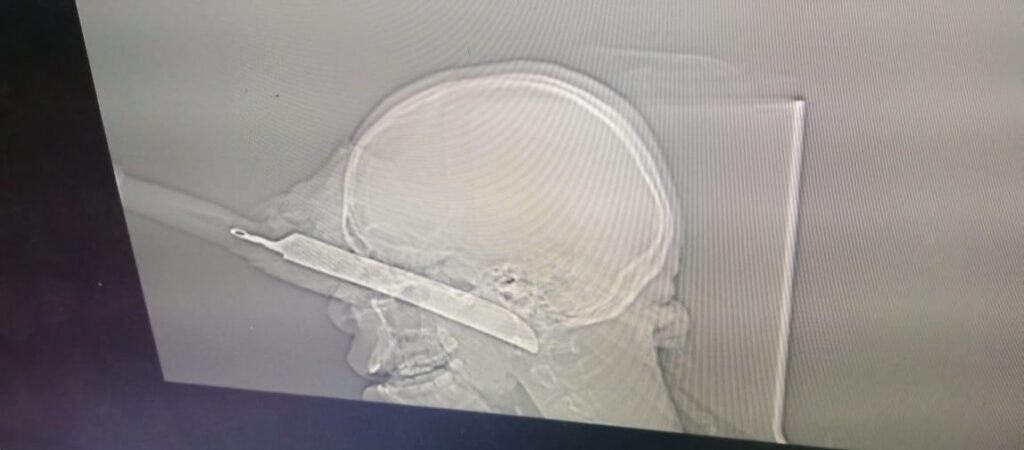

Um cidadão de 21 anos de idade, proveniente da província do Zaire, sobreviveu após 24 horas de viagem com uma faca no olho direito, tendo sido submetido a uma cirurgia, no hospital Josina Machel, em Luanda.

O hospital Josina Machel, a través da sua equipa multidisciplinar composta por cirurgia Maxilo Facial, Otorrinolaringologia, Oftalmologia e Anestesista, operou de urgência neste domingo 24, um jovem de 21 anos de idade transferido da província do Zaire vítima de agressão física com uma arma branca (faca), na tentativa de acudir uma briga em que esteve envolvido o seu irmão.

O jovem foi atingido na face com uma faca de aproximadamente 50 cm que causou sérios ferimentos, entre eles glóbulo ocular direito, que levou mesmo a uma evisceração, que é uma operação realizada para remoção do conteúdo interno do globo ocular, através de curetagem.

A cirurgia levou aproximadamente 5 horas. Segundo o Dr. Agnelo Lucamba, um dos membros da cirurgia afirma que o paciente até ao momento não corre risco de morte, porém, teve muita sorte por sair com vida.